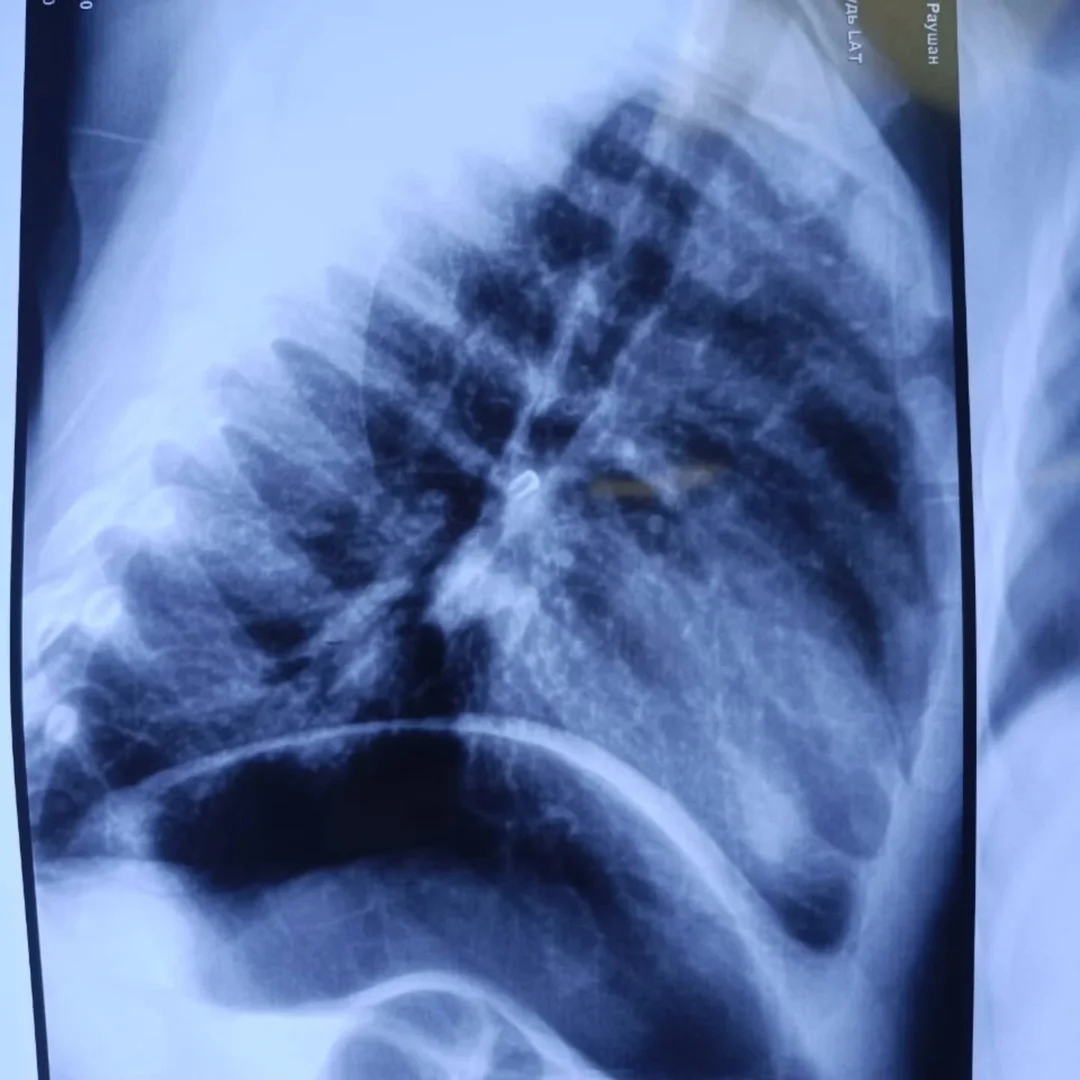

Ооруканага түшкөндө наристенин абалы дем алуу жетишсиздигинен улам оор деп бааланган. Рентгендик изилдөөнүн жыйынтыгында баланын оң бронхасында бөтөн зат бар экени аныкталган. Дарыгерлер ыкчам түрдө наркоз алдында бронхоскопия жасап, өпкөгө тыгылып калган шуруну ийгиликтүү алып чыгышты.